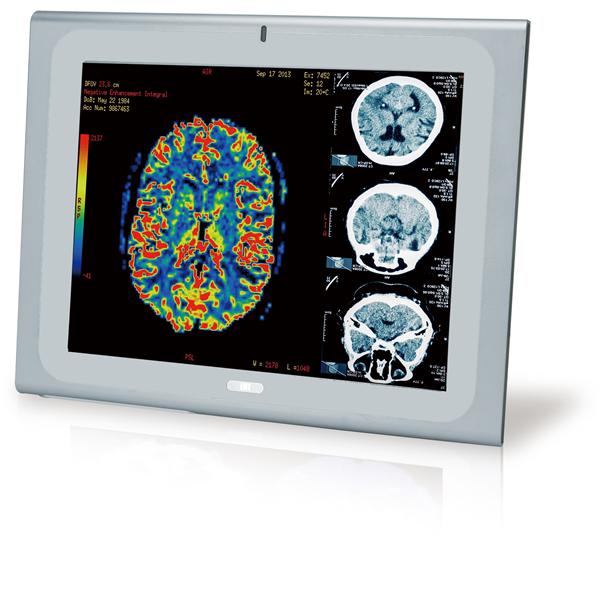

IEI Technology | Panel PCs 21.5" 250cd/m FH... |

IEI Technology | Panel PCs 17" Medical Pan... |

IEI Technology | Panel PCs 19" Medical Pan... |

IEI Technology | Panel PCs 17" Medical Pan... |

IEI Technology | Panel PCs 19" Medical Pan... |

IEI Technology | Panel PCs 17" Medical Pan... |

IEI Technology | Panel PCs 19" Medical Pan... |